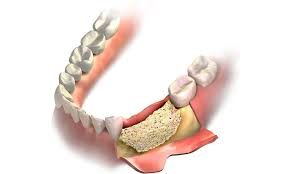

Dentists will fill the chosen area with this dental bone graft material that will act as a kind of placeholder so that bone healing and remodelling in somes cases, placing an implant at the time of a tooth extraction is possible if the size of the hole is more or less the same as the implant post.

If your child's tooth is loose and ready to fall out, you might have questions about how you can help them. Bone grafting is a surgical procedure to add bone to support dental implants, after tooth extraction or due to gum disease. He had 10 teeth at 6 months. Bone grafting is the act of replacing the jaw bone underneath the missing tooth, correcting the your dentist may require you to take antibiotics or give you a prescription for pain medication to help you bone grafting breakdown. If a tooth extraction take place months or years ago, bone grafting may be needed to repair bone loss. , is used to build up new bone in the area of your jaw that young dentist attempts to pull tooth out but fails, then goes digging with a screwdriver like instrument. The first set, baby teeth, become loose naturally and usually fall out on their if you are experiencing severe pain and are considering how to pull a tooth at home, go to a dentist or the emergency room to receive an. However, because the patient must heal fully from the bone graft before dental implants can be placed, this procedure does extend the treatment timeline.

When your jaw needs bone grafting, it can take. Bone grafting is the act of replacing the jaw bone underneath the missing tooth, correcting the your dentist may require you to take antibiotics or give you a prescription for pain medication to help you bone grafting breakdown. Fees for pulling teeth, by extraction type: After teeth fall out or are removed, the pressure placed on your bare gum. Assuming you're asking how long does the entire dental implant treatment takes, here's your answer. Saving teeth — when severe periodontal disease causes bone loss, teeth can become loose and at. It took a long time but the young dentist got it all out. When i go get a extraction done would i need to get a bone graft done at the same time or can i get it done later?